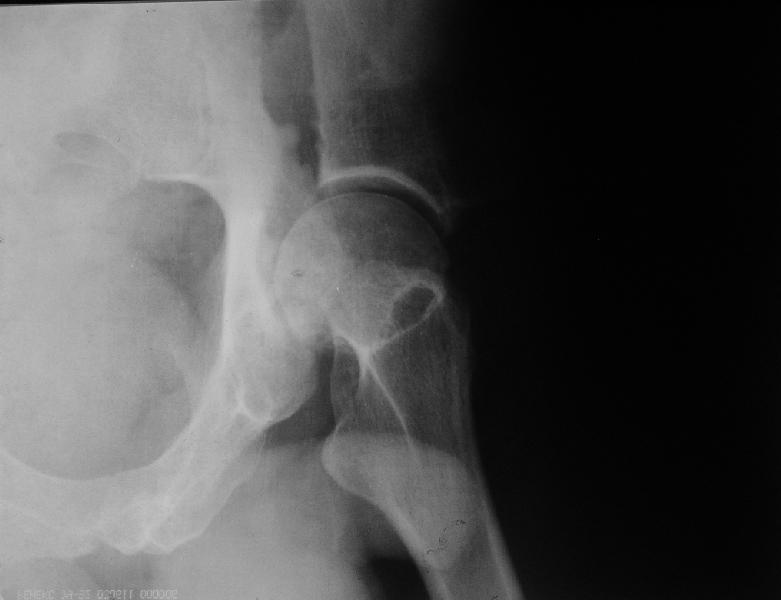

Несросшийся перелом вертлужной впадины

мужчина, 43 лет, получил травму в январе 2001 года. Лечился консервативно, в соседней области: скелетное вытяжение 6 недель, далее в кокситной гипсовой повязке 2 месяца. С декабря 2001 года ходит без дополнительной опоры, с компенсацией имеющегося укорочения - 4 сантиметра. С марта этого года беспокоят боли, усиливающиеся после умеренной физической нагрузки, возникающие в задних отделах таза и переходящие в область тазобедренного сустава. По данным ретгенографии и компьютерной томографии у больного имеется несросшийся высокий двухколонный перелом вертлужной впадины. Заранее спасибо.